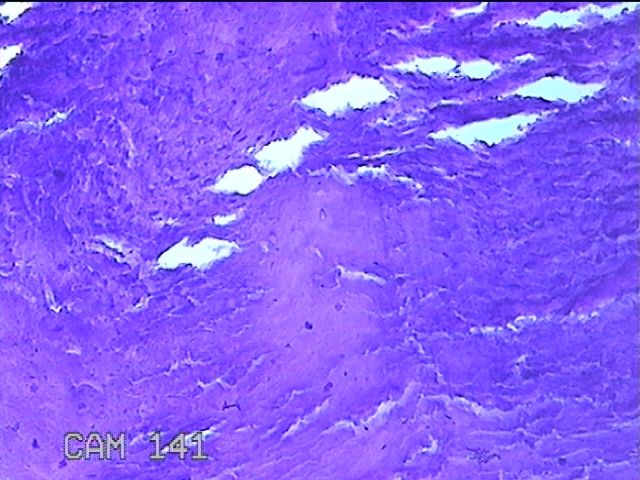

右侧拇指掌侧结节

性别

女

年龄

25岁

临床诊断

皮下结节

一般病史

发现右侧拇指结节2个月余。

标本名称

大体所见

灰白粉红色带皮肤样结节1.5x0.5x0.3cm一个,表面糜烂,切开结节呈实性,切面灰白粉红色,质软。